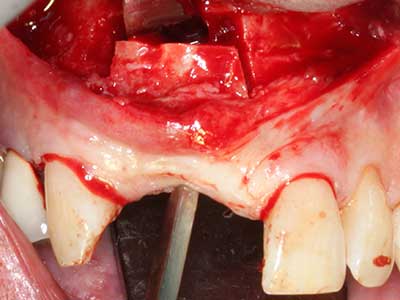

Пиезохирургията има допълнителни предимства при събиране на костни блокове. В допълнение към високата прецизност при остеотомията, описана по-горе, употребата на фините режещи накрайници значително намаляват загубата на материал. Голяма загуба на материал по време на събиране може да се очаква с дебелите накрайници, особено при употреба на борери Линдеман (Lakshmiganthan, Gokulanathan et al. 2012). Базалното разделяне, което е необходимо, особено за присадка на блок при ретромолар, е улеснено от специално създадени правоъгълни триони. В резултат на това, пиезохирургията е разглеждана като прецизна, улеснена и безопасна процедура за събиране на костни блокове в ретромоларното пространство (Happe 2007) (Фиг. 1-12).

Фиг. 1: Препарация на костно покритие с Piezomed (W&H Залцбург, Австрия).

Фиг. 2: Хоризонтален и вертикален латерално-максиларен дефект с висока линия на усмивката с индикация за пре-реконструкция за имплант.

Фиг. 3: Базалното разделяне на блока е по-лесно със специалните извити накрайници.

Фиг. 6: След препарация на мукопериосталната клапа.